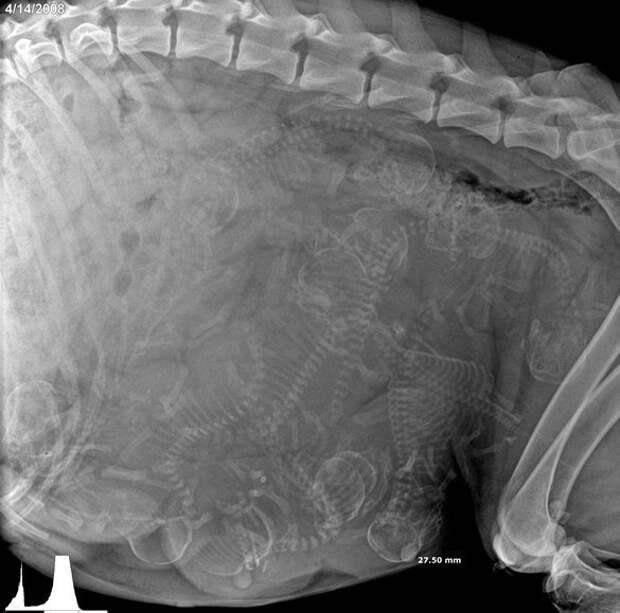

1. Беременная собака